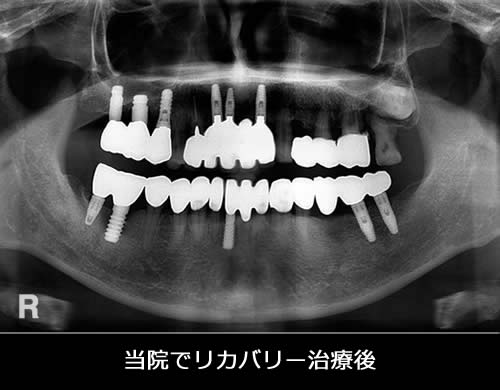

当院でリカバリーした患者さんをご紹介します。この患者さんは、他医院でインプラント治療をしたもののうまく噛めず、Dr.に相談しても取り合ってもらえず当院にいらっしゃいました。その後、当院で診断した結果インプラント治療だけではなく、全顎的に治療が必要と判断し咬み合わせを再構成する治療を行いました。患者さんとの約束である「前歯でトウモロコシを噛む」という公約も無事果たせて嬉しく思っています。

- 治療期間:26ヶ月

- 治療回数:155回

- 費用:インプラント治療:160万円 補綴治療:70万円

- リスク:メンテナンスを怠ると、インプラント周囲炎になる可能性があります。

- インプラント手術には合併症が伴う場合があります。

- 治療期間は治癒の状態により前後する場合があります。